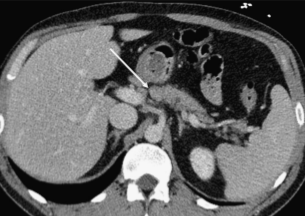

(Слева) На аксиальной КТ с контрастным усилением определяется гиподенсный участок (разрыв) в средних отделах тела поджелудочной железы. Обратите внимание на небольшое количество жидкости позади поджелудочной железы поблизости от селезеночной вены.

(Справа) На аксиальной КТ с контрастным усилением у этого же пациента на более каудальном уровне также определяется разрыв поджелудочной железы; жидкость возле ее края становится более очевидной. У некоторых пациентов наличие жидкости позади поджелудочной железы является наиболее очевидным признаком ее разрыва.